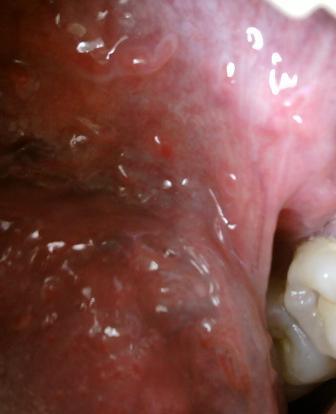

如何分辨真假尖锐湿疣现在假性尖锐湿疣是一种新兴的疾病,很多患者由于治病心切,会盲目诊治,因此会出现误诊误治现象的发生,临床上有些会把假性尖锐湿疣误认为尖锐湿疣。尖锐湿疣一般通常发病于年轻的男女,而假性尖锐湿疣通常发病于30岁以及以上的人,尖锐湿疣属于病毒性疾病,病毒比较顽固吗,具备传染性,而假性尖锐湿疣是一种良性病毒,不具备传染性,尖锐湿疣对于人体健康危害比较大,而假性尖锐湿疣危害则比较小。